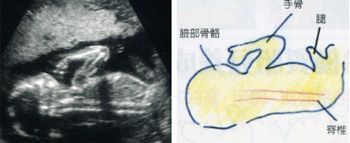

图解怀孕中期b超(13-24周)